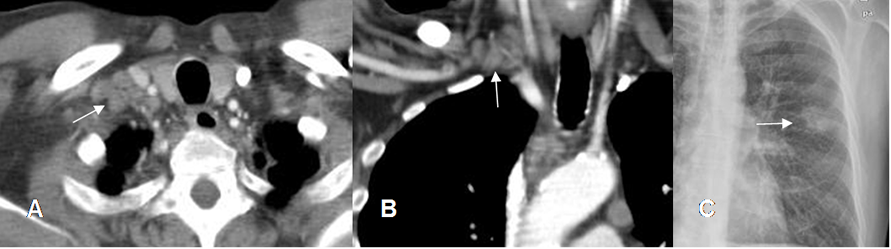

Fig 13. Tumor metastásico.

A: TAC axial, B: TAC reconstrucción coronal con contraste y C: Rx PA. Adenopatías que ocupan el espacio interescalénico, por metástasis contralateral de neoplasia pulmonar.